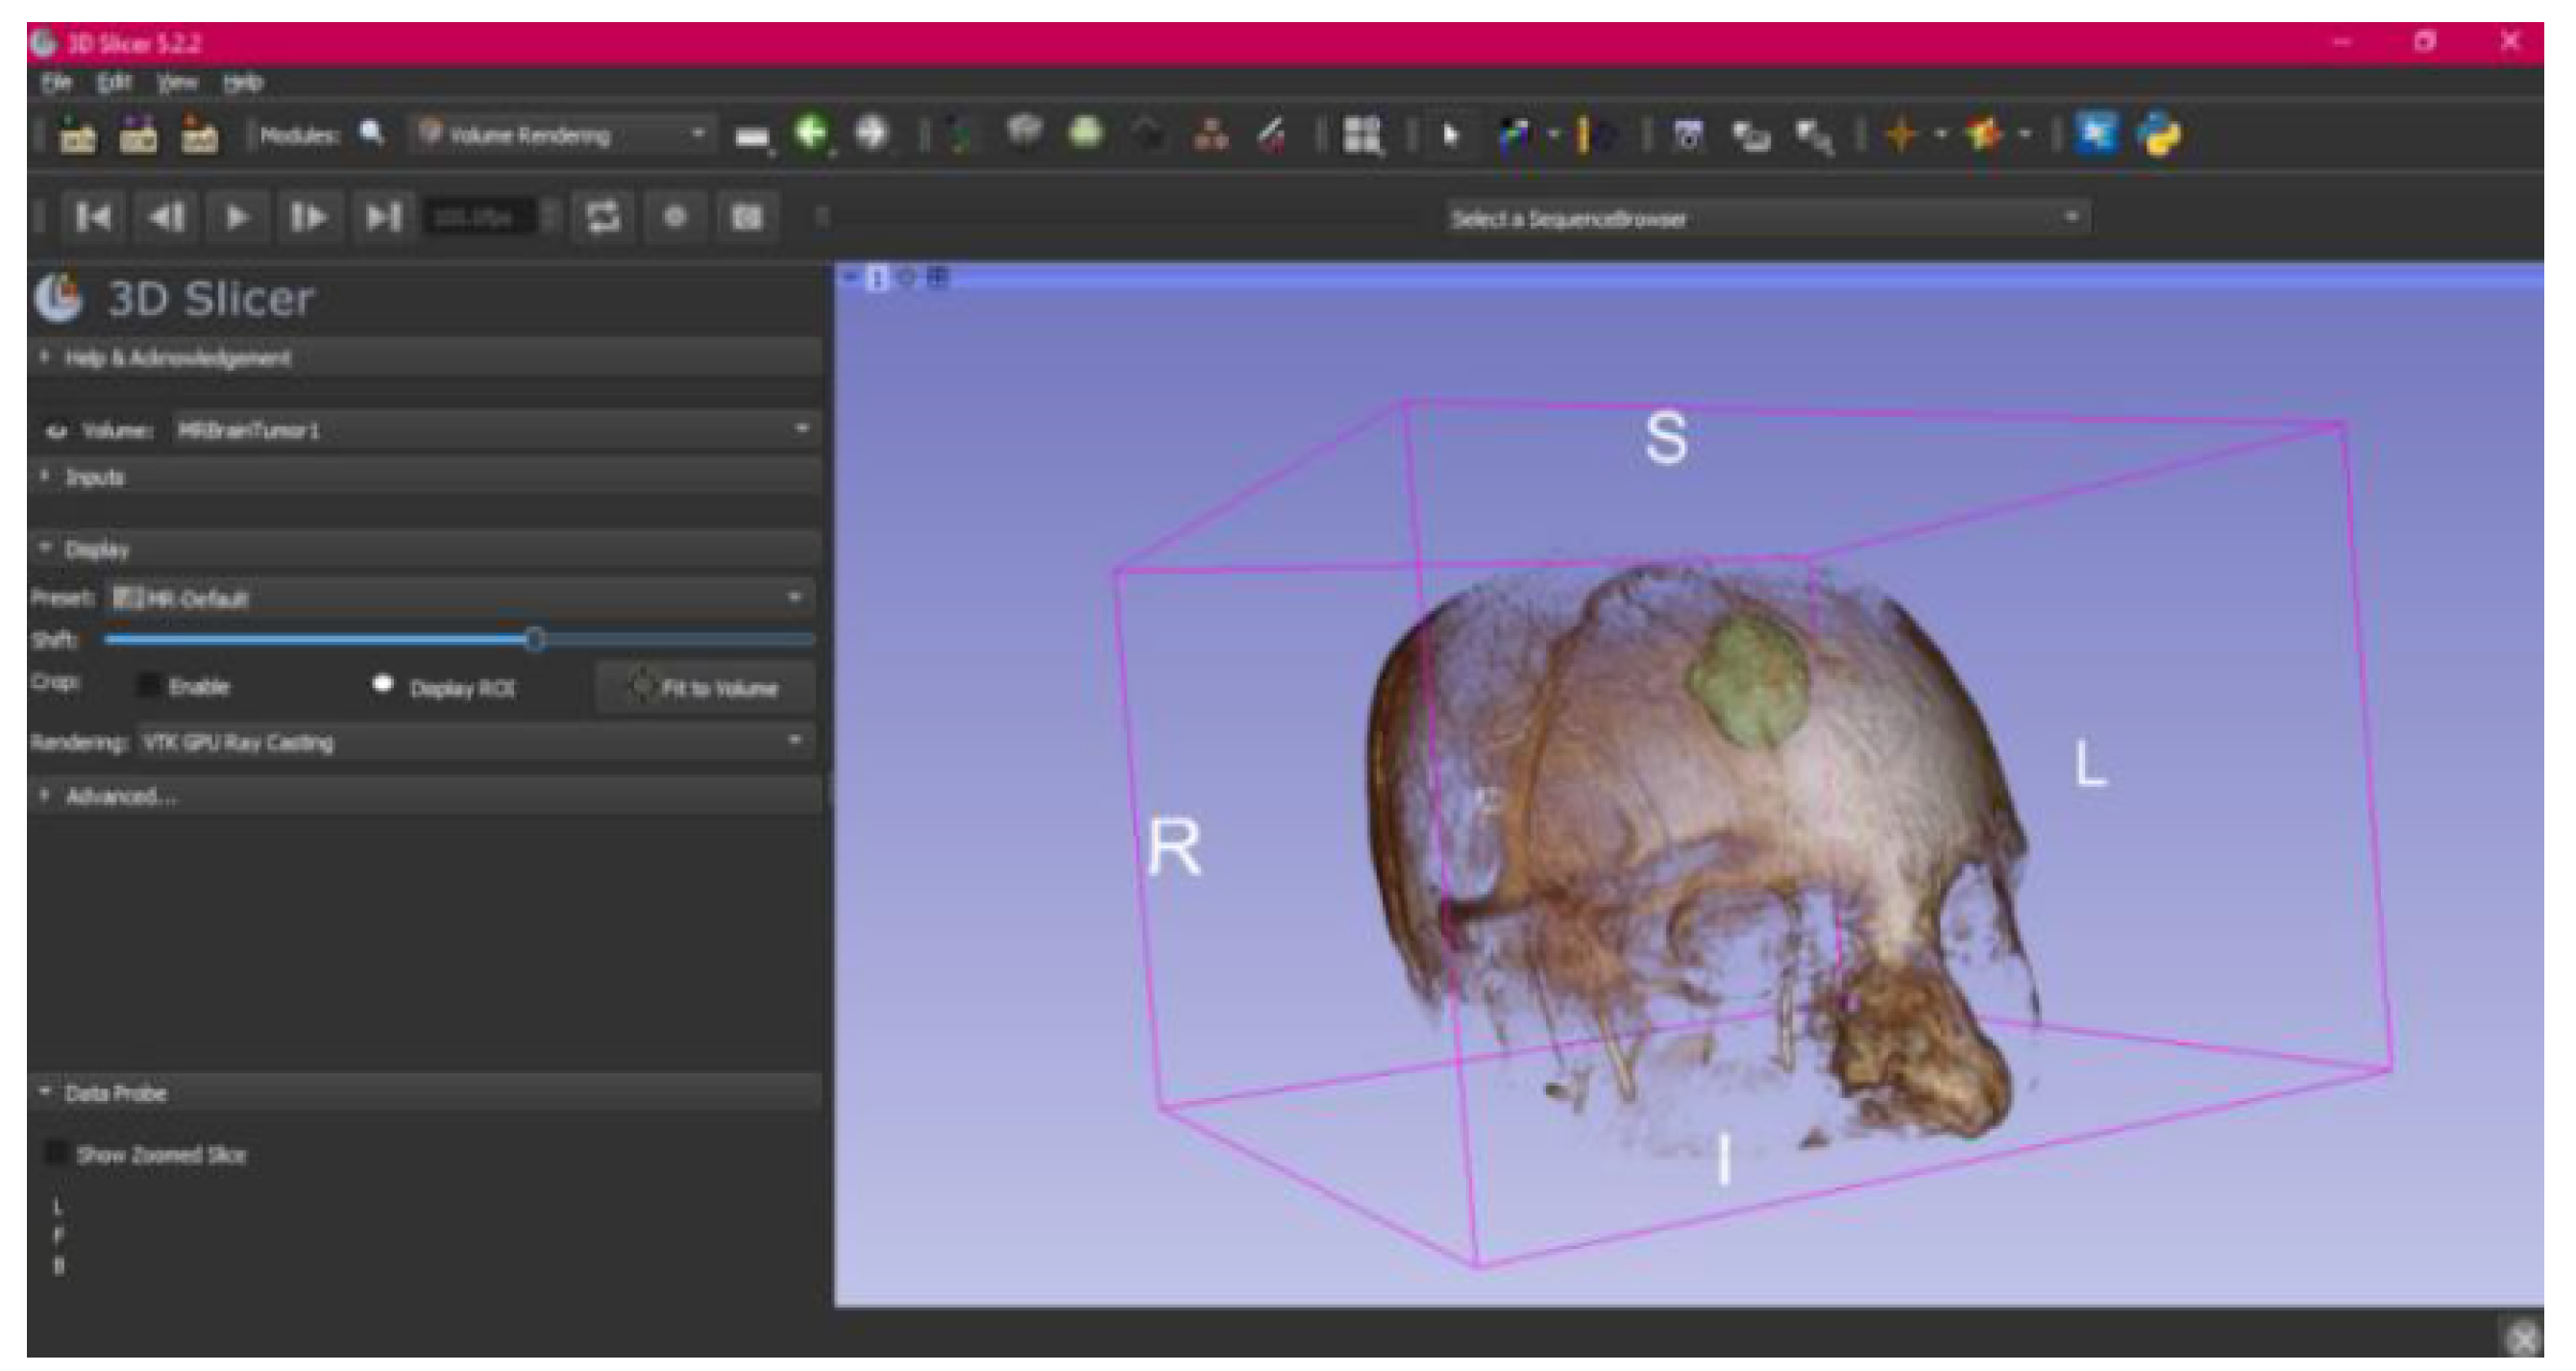

- Select the “Volume Rendering” module in the toolbar.

- Select the volume of interest in the drop-down menu, and activate the rendering function.

- Configure the rendering process by accessing the “Display” drop-down. Choose the most appropriate “preset” option in terms of the image and anatomical model tissue.

- Use the Shift function to adjust the rendered visible tissues, and enable the “Crop” option in order to cut the “region of interest”.

- Make the Region of Interest (ROI) display visible in order to visualise it, and adjust the ROI volume rendering square in the region of interest for the 3D view.

3.3. Human Brain Tumour

3.3.1. DICOM-to-STL Files